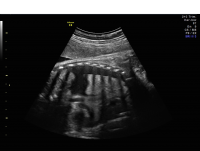

Hydrothorax